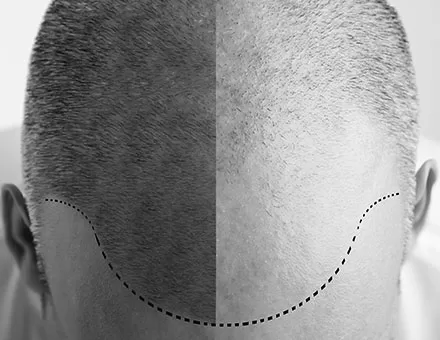

ΧΩΡΙΣ ΓΡΑΜΜΙΚΗ ΟΥΛΗ – ΧΩΡΙΣ ΡΑΜΜΑΤΑ

ΦΥΣΙΚΟ ΑΠΟΤΕΛΕΣΜΑ

ΕΜΦΥΤΕΥΣΗ ΑΠΟ ΔΡ. ΔΙΟΝΥΣΙΟΥ

Τοποθέτηση

Εμφύτευση Τριχοθυλακίων

Η τεχνική μεταμόσχευσης μαλλιών FUE, σε αντίθεση με άλλες τεχνικές, επιτυγχάνει πάνω από 95% βιωσιμότητα των μοσχευμάτων και διατήρηση των εμφυτευμένων τριχών σε Α – Β Ζώνη. Σε μία μόνο επίσκεψη, μπορούμε να μεταμοσχεύσουμε πάνω από 2500 μοσχεύματα (περίπου 6500 τρίχες), πετυχαίνοντας τη μέγιστη δυνατή πυκνότητα.